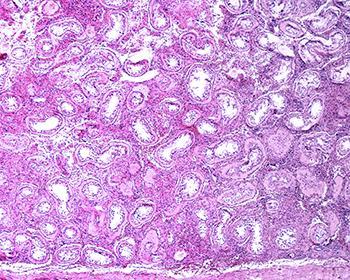

Klinefelter syndrome (KS) is one of the most common chromosomal abnormalities, affecting approximately 1 in 500 to 1 in 1,000 males. KS is typically characterized by an extra X chromosome, resulting in a karyotype of 47,XXY, though variants exist. One of the most significant clinical features of KS is infertility, with over 95% of KS patients being azoospermic (having no sperm in the ejaculate). This infertility arises because of progressive degeneration of the seminiferous tubules and Sertoli cells, which ultimately leads to a depletion of germ cells, the precursors to sperm. However, advances in reproductive medicine have offered new hope for fertility preservation in these individuals, particularly through early interventions.

Once KS patients reach adolescence and adulthood, fertility preservation becomes more challenging because of the progressive degeneration of germ cells and the accompanying fibrosis of the testicular tissue. Despite this, there are still options for sperm retrieval and cryopreservation in post-pubertal KS individuals.